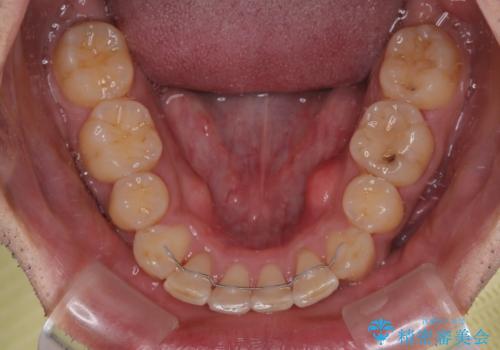

飛び出した前歯を治したい ワイヤー装置での抜歯矯正

- 上下ともに前歯2本が著しく飛び出している状態を気にして来院された患者様です。

唇の閉じにくさが認められたため、上下左右の小臼歯を1本ずつ、計4本を抜歯してワイヤー装置にて矯正治療を行うこととしました。

左上は、定石として抜歯される第一小臼歯の代わりに、神経が除去されている第二小臼歯を抜歯することとしました。

セオリーから外れた治療となるため、補助装置などを使用してよりよい仕上がりを目指すこととしました。

第二小臼歯を抜歯したことだけでなく、非常に強い咬合力もあり、治療期間は非常に長期となりましたが、しっかりと仕上げることができました。